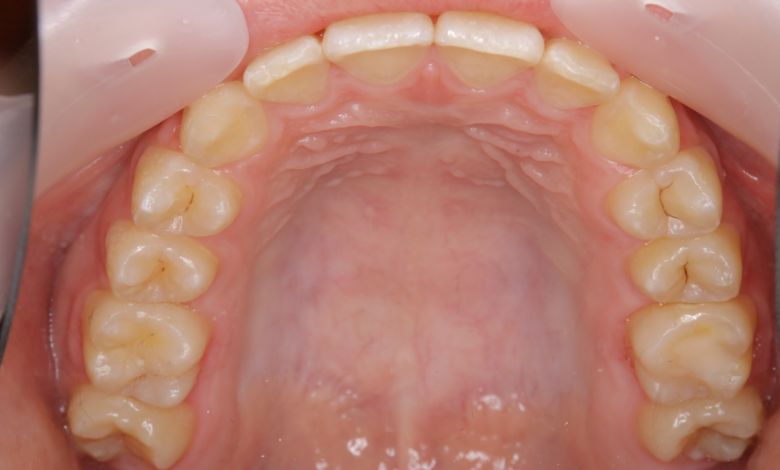

前歯の重なりが強く、他院では「上下4本の抜歯が必要」と診断されたとのことで、当院にご相談にいらっしゃいました。

歯並びがV字型で歯茎の土手(歯列弓)が狭く、歯が並ぶスペースが狭い

歯並びがU字型になって、歯茎の土手(歯列弓)が広くなった。

前歯の重なりが大きい

前歯の重なりがなくなって、綺麗な歯並びになった。

一本がかなりの出歯に

出歯は解消している。

下顎の歯が凸凹している

下顎の歯が整ってきれいにならんでいる

治療前は前歯の重なりが強く見られましたが、歯茎の土手(歯列弓)そのものを広げる治療を行うことで、上下ともにV字型だった歯列が自然なアーチ型へと拡大し、結果的に無理なく歯列を整えることに成功しました。